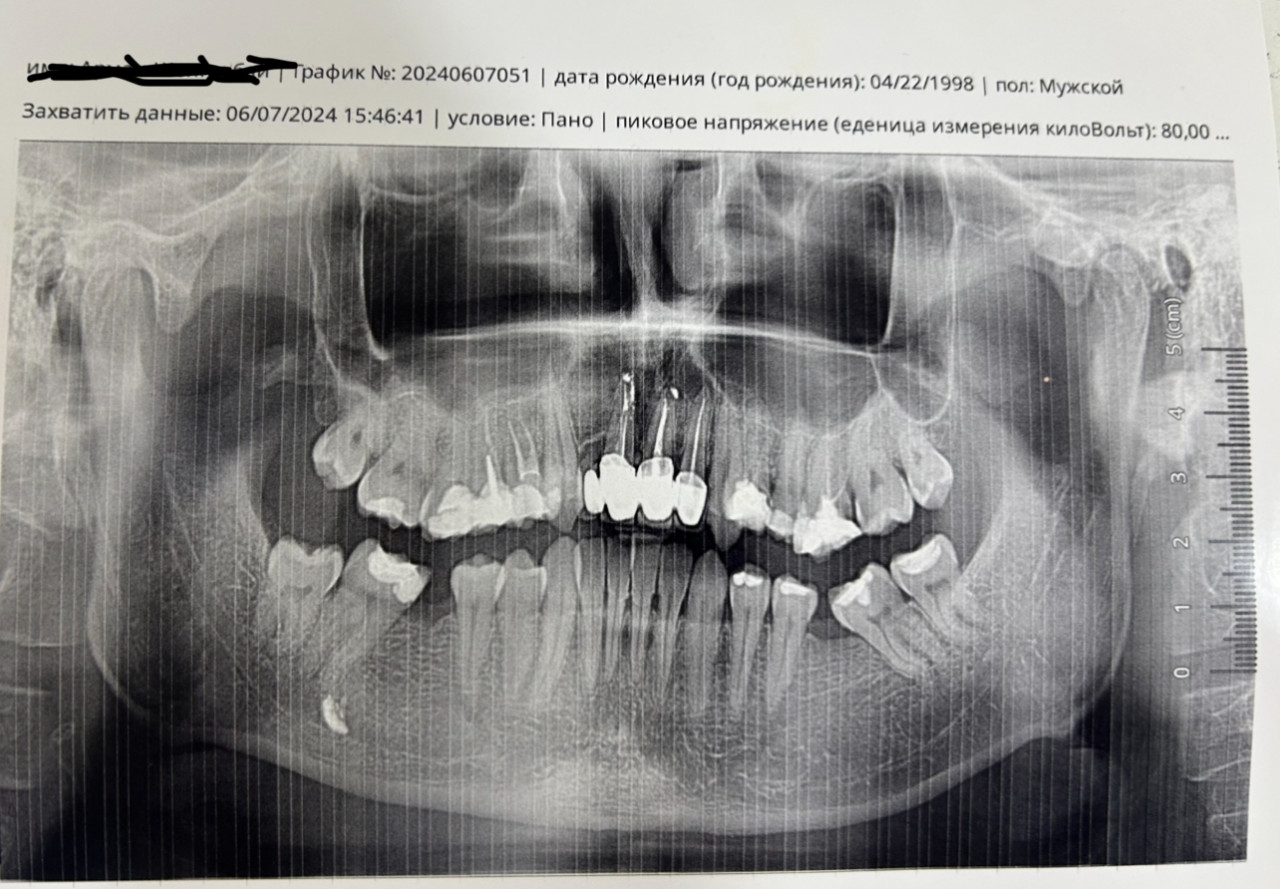

У меня был уже ранее вопрос но тут я хочу приложить снимок до того как я удалил 3 зуба мудрости (2 верхних и один нижний справа) и поставил брекеты. Прошу ответить аномалия прикуса на костном (черепном) уровне где требуется операция?

Здравствуйте. По представленному панорамному снимку выраженной асимметрии нижней или верхней челюсти не видно т.е линии челюстей симметричны, тело и ветви нижней челюсти примерно одинаковой высоты и ширины.

Смещение подбородка или значительного перекоса костей не прослеживается.

Аномалия прикуса по панорамному снимку полностью не оценивается и для этого необходима телерентгенограмма (ТРГ) головы в боковой и прямой проекциях и клинический осмотр. По этому снимку можно сказать, что возможны незначительные зубоальвеолярные отклонения, но не костная деформация, требующая операции.